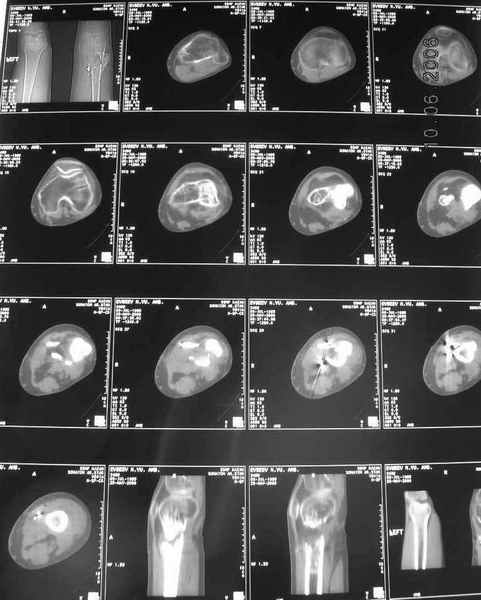

Рефрактур уж точно можно будет не опасаться, а за несколько месяцев даже при отсутствии заполнения костью по всей окружности, этот обходной "мостик" упрочнится и возьмет на себя нагрузку. В приложении пример такого рода "эндопротезирования диафиза", прошло больше 3 лет.